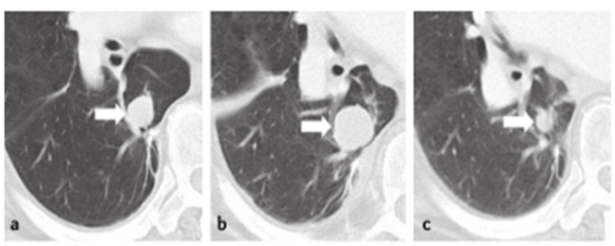

зӣёиҫғд№ӢдёӢ����пјҢз ”з©¶иҖ…иҜ„дј°иҷҪ然еҸҜиғҪдјҡеўһж·»еҒҸеҖҡзҡ„еҸҜиғҪжҖ§����пјҢдҪҶи¶ҠеҸ‘й«ҳж•Ҳ����пјҢз ”з©¶иҖ…д№ҹдјҡжӣҙзӣёиҜҶжӮЈиҖ…зҡ„зңҹзңҹзӣёеҪў����пјҢиғҪеҮӯиҜҒжӮЈиҖ…зҡ„зҠ¶жҖҒжқҘиҜ„дј°еҪұеғҸеӯҰиө„ж–ҷзҡ„еҸҜйқ жҖ§����пјҢжӣҙжңүеҲ©дәҺеҒҡеҮәеҗҲзҗҶзҡ„гҖҒеҲҮеҗҲжӮЈиҖ…еҲ©зӣҠзҡ„иҜ„дј°����пјҢиҝҷз§ҚдјҳеҠҝеңЁиӮҝзҳӨе…Қз–«жІ»з–—жіӣиө·еҒҮжҖ§еёҢжңӣж—¶е°ӨдёәзӘҒеҮәпјҲеӣҫ3пјү����пјҢжӯӨж—¶IRCеӣ дёҚеҸҜе‘Ёе…ЁзӣёиҜҶжӮЈиҖ…зҡ„дёҙеәҠжғ…еҪў����пјҢеҸҜиғҪйҡҫд»ҘеҜ№жӮЈиҖ…зҡ„жІ»з–—ж•ҲжһңдёҫиЎҢе……еҲҶиҜ„дј°��гҖӮ

еӣҫ3. 77еІҒз”·жҖ§����пјҢжҷҡжңҹзҺ„иүІзҙ зҳӨжӮЈиҖ…����пјҢжҺҘеҸ—lpilimumabжІ»з–—пјҡпјҲaпјүеҹәзәҝжңҹCTжҸҗйҶ’з—…зҒ¶19mm����пјҢпјҲbпјүжІ»з–—12е‘ЁеҗҺ����пјҢCTжҸҗйҶ’з—…зҒ¶иҫҫ29mm����пјҢдёҺеҹәзәҝзӣёжҜ”еўһеӨ§53%����пјҢпјҲcпјүжІ»з–—24е‘ЁеҗҺ����пјҢCTжҸҗйҶ’з—…зҒ¶зј©е°ҸиҮі12mm����пјҢжҖқйҮҸеҒҮжҖ§еёҢжңӣеҸҜиғҪ��гҖӮ